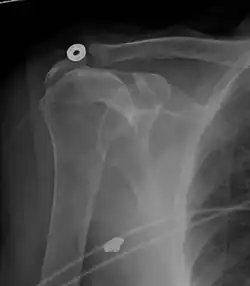

Projectional radiograph of normal glenohumeral position.[51]

High-riding humeral head in a rotator cuff tear.

X-ray projectional radiography cannot directly reveal tears of the rotator cuff, a 'soft tissue', and consequently, normal X-rays cannot exclude a damaged cuff. However, indirect evidence of pathology may be seen in instances where one or more of the tendons has undergone degenerative calcification (calcific tendinitis). The humeral head may migrate upward (high-riding humeral head) secondary to tears of the infraspinatus, or combined tears of the supraspinatus and infraspinatus.[51] The migration can be measured by the distance between:

• A line crossing the center of a line between the superior and inferior rims of the glenoid articular surface (blue in image).

• The center of a "best-fit" circle positioned over the humeral articular surface (green in image)

Normally, the former is positioned inferiorly to the latter, and a reversal therefore indicates a rotator cuff tear.[51] Prolonged contact between a high-riding humeral head and the acromion above it may lead to X-ray findings of wear on the humeral head and acromion; secondary degenerative arthritis of the glenohumeral joint (the ball and socket joint of the shoulder), called cuff arthropathy, may follow.[50] Incidental X-ray findings of bone spurs at the adjacent acromioclavicular joint may show a bone spur growing from the outer edge of the clavicle downward toward the rotator cuff. Spurs may also be seen on the underside of the acromion, once thought to cause direct fraying of the rotator cuff from contact friction, a concept currently regarded as controversial.